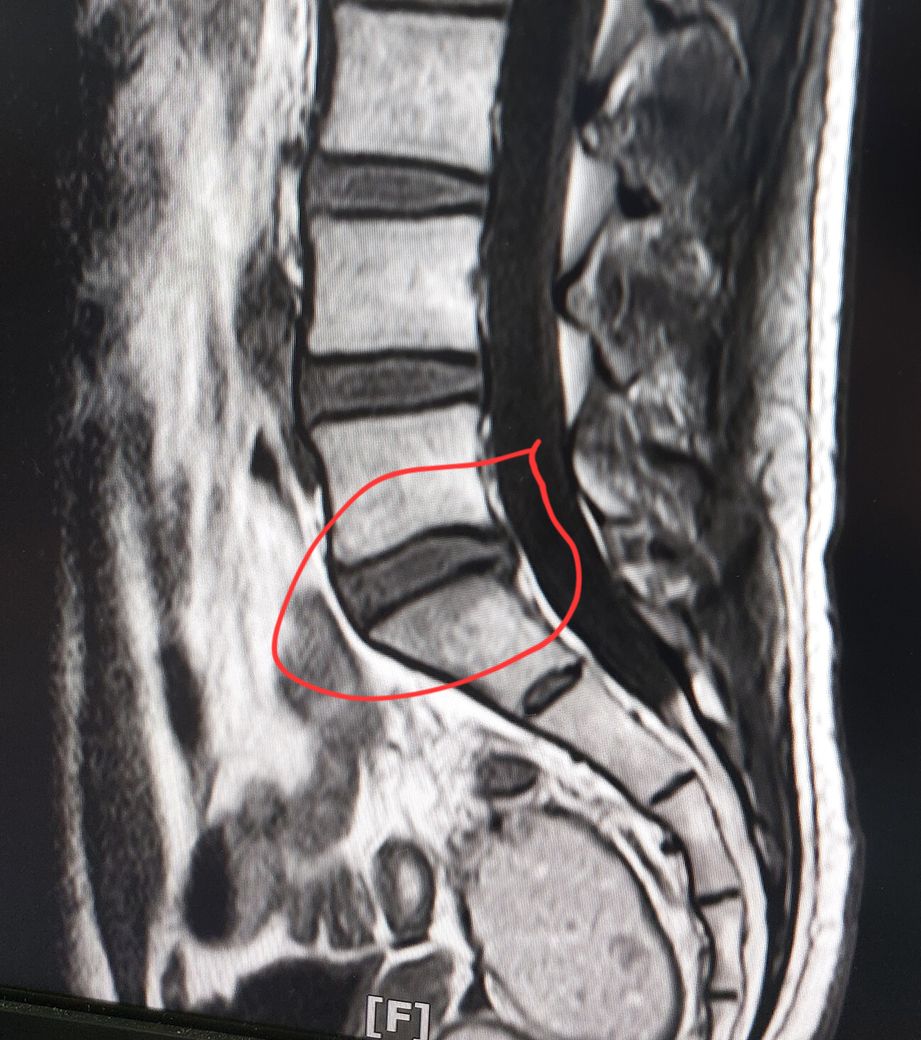

사진은 제 mri입니다